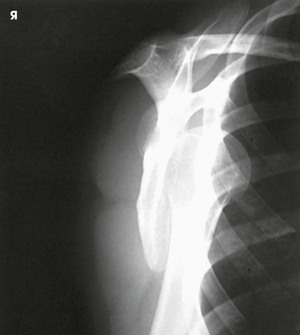

This projection, described by Rubin et al.,1 obtained its name as a result of the appearance of the scapula. The body of the scapula forms the vertical component of the Y, and the acromion and the coracoid process form the upper limbs. This projection is useful in the evaluation of suspected shoulder dislocations.

The scapular Y is shown on an oblique image of the shoulder. In the normal shoulder, the humeral head is directly superimposed over the junction of the Y (Fig. 5-37). In anterior (subcoracoid) dislocations, the humeral head is beneath the coracoid process (Fig. 5-38); in posterior (subacromial) dislocations, it is projected beneath the acromion. An AP shoulder projection is shown for comparison (Fig. 5-39).